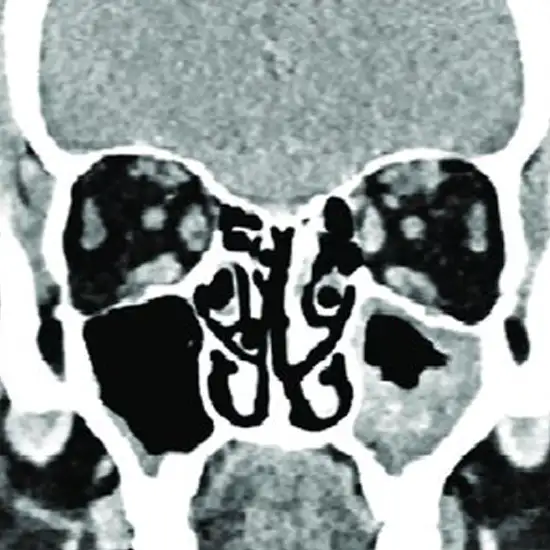

CECT Right Orbit is contrasted with enhanced computed tomography of the right orbit. It is an imaging scan that uses contrast media, an X-ray beam, and a computer to produce images of the right eye socket, right eye, and surrounding area. This scan helps diagnose injury, diseases, and congenital defects. Doctors recommend this scan to detect the broken right eye socket area and foreign objects in the right eye.

You will be given contrast media which is a special dye before the examination through IV. The technologist will ask you to lie straight and still. A rotating X-ray beam is used to create the image's right eye socket, right eye, and surrounding area.